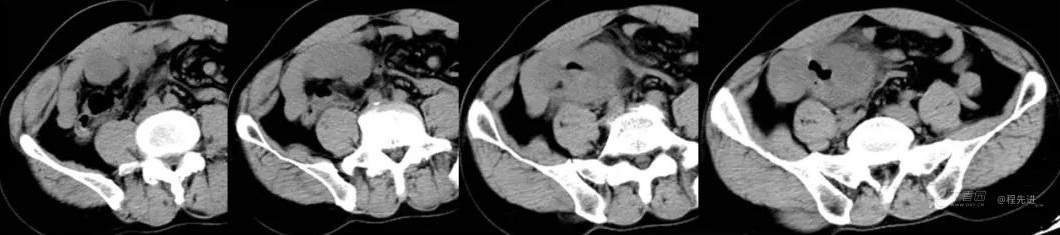

CT平扫